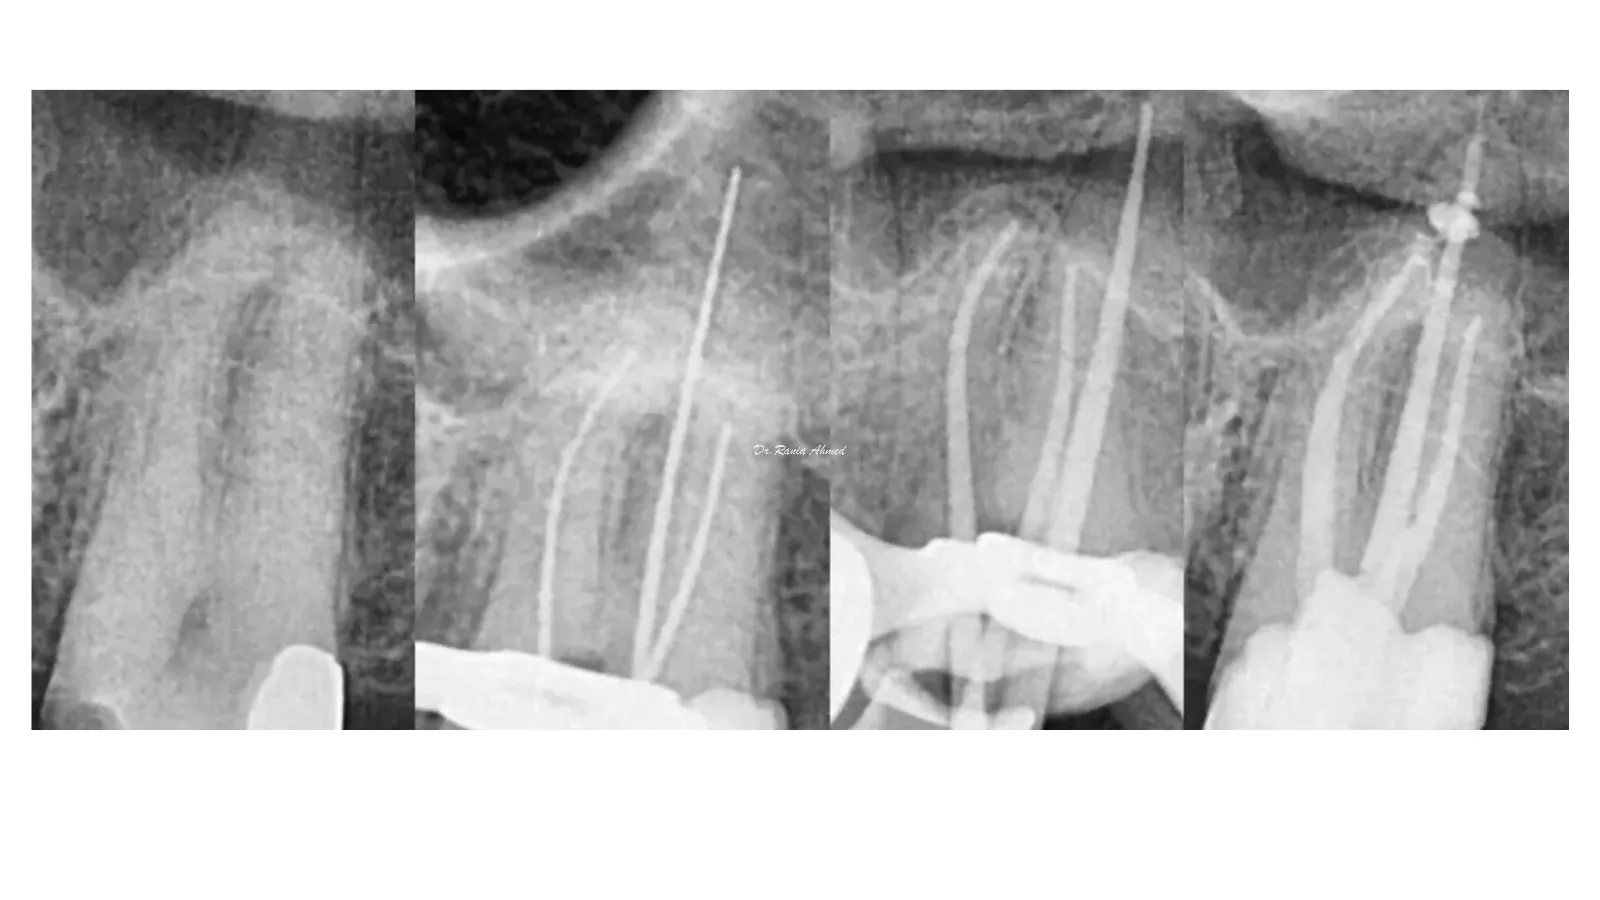

Endodontic Treatment